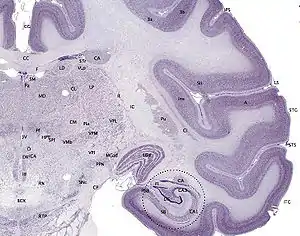

In a cross-section of the hippocampus, including the dentate gyrus, several layers will be shown. The dentate gyrus has three layers of cells (or four if the hilus is included). The layers are from the outer in – the molecular layer, the inner molecular layer, the granular layer, and the hilus. The CA3 in the hippocampus proper has the following cell layers known as strata: lacunosum-moleculare, radiatum, lucidum, pyramidal, and oriens. CA2 and CA1 also have these layers except the lucidum stratum.[23][24]